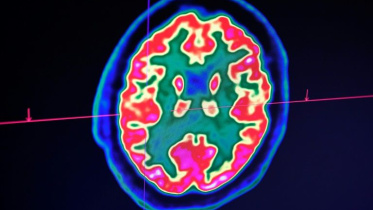

Confusion, seizure, strokes: How Covid-19 may affect the brain

A pattern is emerging among Covid-19 patients arriving at hospitals in New York: Beyond fever, cough and shortness of breath, some are deeply disoriented to the point of not knowing where they are or what year it is.